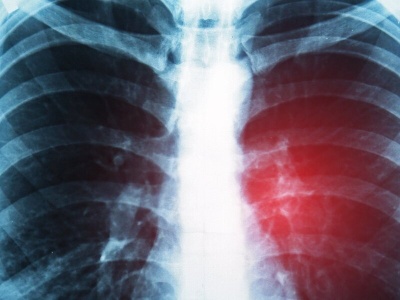

Rak drobnokomórkowy płuca przez lata uchodził za nowotwór bez skutecznego leczenia. – To najbardziej agresywna postać raka płuca, ale dziś mamy terapię, która niemal dwukrotnie wydłuża życie pacjentów – mówi prof. Damian Tworek, onkolog kliniczny, podkreślając znaczenie szybkiej diagnostyki i Lung C...

Polska Grupa Raka Płuca i sygnatariusze Misji Rak Płuca zaprezentowała zaktualizowaną edycję „Misji Rak Płuca 2024–2034”. Opracowanie wskazuje największe bariery organizacyjne i kliniczne oraz prezentuje kluczowe rekomendacje zmian.

„Badania NDTK pozwalają wykrywać raka płuca w bardzo wczesnym stadium. To postęp w polskiej onkologii”.

Radioterapia może przełamać oporność na immunoterapię w niektórych rakach płuca – wynika z badania opublikowanego w „Nature Cancer”. Artykuł Radioterapia może przełamać oporność na immunoterapię w raku płuca pochodzi z serwisu Alert Medyczny.